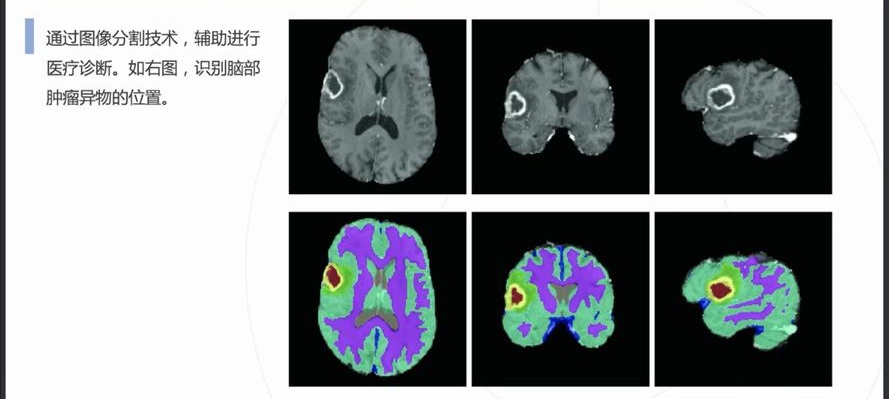

自动病灶检测:借助计算机视觉和人工智能算法,CCD视觉检测设备能够自动识别医学影像中的病灶区域,如肿瘤、炎症、骨折等异常结构。

早期癌症筛查:在乳腺癌、肺癌、皮肤癌等癌症的早期筛查中,CCD视觉检测系统通过分析X光、MRI或CT扫描图像,识别出肿瘤的早期迹象,显著提高早期诊断率。